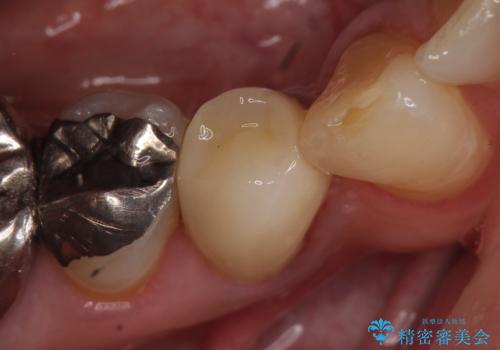

- 他院にて右下4番目の歯の再根管治療が必要だと言われた方の症例です。

再根管治療終了後、オールセラミッククラウンによる補綴を行いました。

今回用いたオールセラミッククラウンは、ジルコニアフレームという白い素材の上にセラミックを盛っているため審美性が非常に高いのが特徴です。

またジルコニアは人工ダイヤモンドの材料にも使われているほど高い強度を持っており、そのためオールセラミッククラウンは審美性だけでなく、奥歯やブリッジの補綴も可能とするクラウンです。